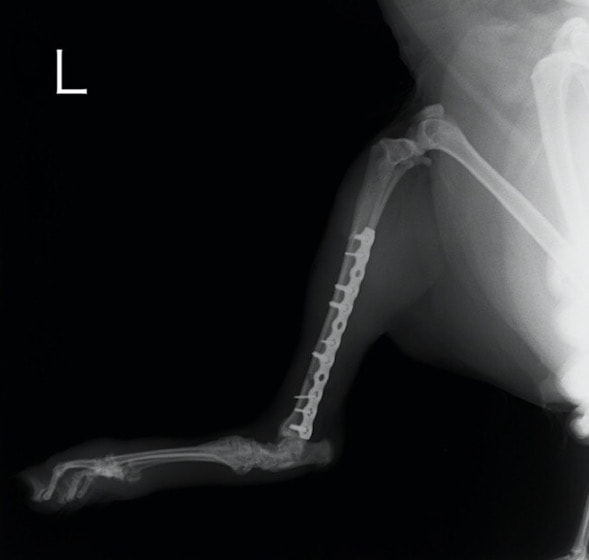

ペルシャ猫 11ヶ月齢 雄

他院にて左大腿骨遠位の成長板骨折(salter-harrisⅠ型)が認められており、治療相談を目的として来院。当院にて、キルシュナーワイヤーを用いたピンニングにより骨折部位の整復を行いました。術後の経過は良好で、現在も経過観察中です。

術後レントゲン

Arthrex社のターゲティングデバイスを用いてピンニングの位置を調整することで、確実な固定を行っています。当院ではこの手術器具以外にも、人の手術にも使用される様々な器具を導入し、手術精度を高め、また医療メーカーと新しい器具の開発、試作にも取り組んでおります。